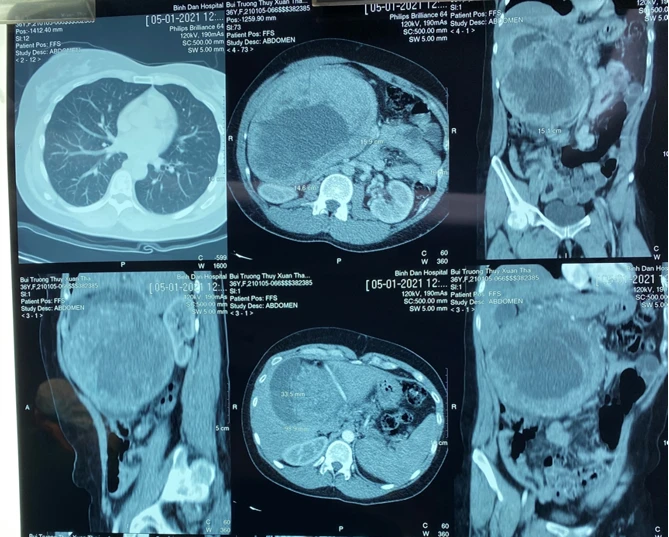

Tại đây, qua thăm khám và làm các chẩn đoán hình ảnh, các BS phát hiện bệnh nhân có khối u đầu - thân tụy khổng lồ xâm chiếm hết vùng bụng bên phải, chèn ép cuống gan và các mạch máu xung quanh.

Khối u tụy to, chèn ép các cơ quan. Ảnh: BVCC